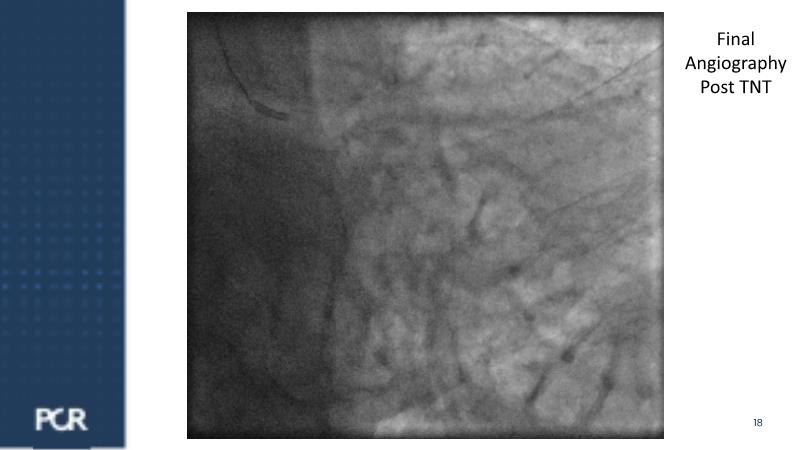

Watch this session for insights into managing acute coronary syndrome patients with multivessel disease, updates on treatment approaches, comparing FULL RESVAC with previous trials like COMPLETE or FIRE, for example, and information on ongoing trials such as FRAMI-AMI 2 and 3. Explore the LIVE case presentation for tailored strategies in post-ACS multivessel disease management, approaches for high bleeding risk patients, and the role of intracoronary imaging in guiding procedures.